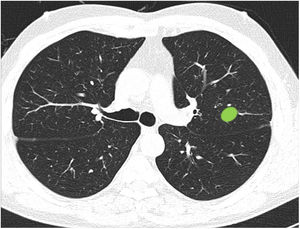

Most respondents (78.6%) were able to classify a central lesion in the absence of dividing lines (image 12), with no significant differences between specialties (Table 3). Similarly, age, sex, or direct involvement in the management of patients with lung cancer did not influence the answer to any of the questions.

Ability to correctly identify a central node in the absence of dividing lines (Figure 12). Most respondents can correctly identify a central lesion (green boxes) in the absence of the dividing lines. No significant differences were observed between groups.

Ability to properly classify a lesion in a site between central and peripheral in the absence of dividing lines (Fig. 3): this block evaluated the uniformity of criteria for classifying a lesion as central (according to a definition of centrality [in the inner two thirds] previously established in the text of the question]) in the absence of dividing lines.